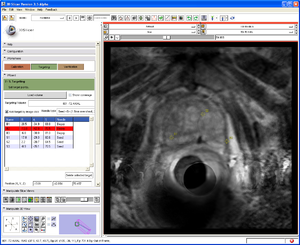

The transrectal prostate robot visualization inside SLICER.

The primary goal for the roadmap is to develop an interventional module for Slicer3 for MRI-guided prostate biopsies. This module and the accompanying tutorial will serve as a template for interventional applications with Slicer3. The module will provide the necessary functionality for calibrating the robot to the MR scanner, planning biopsies, computing the necessary robot trajectory to perform each biopsy, and verification via post-biopsy images. We will obtain a biopsy plan from multi-parametric endorectal image volumes, executable with an existing prostate biopsy device. The system will be will be implemented under Slicer3 as an interactive application.

Calibrate and register robot markers

Close-up of 3D view